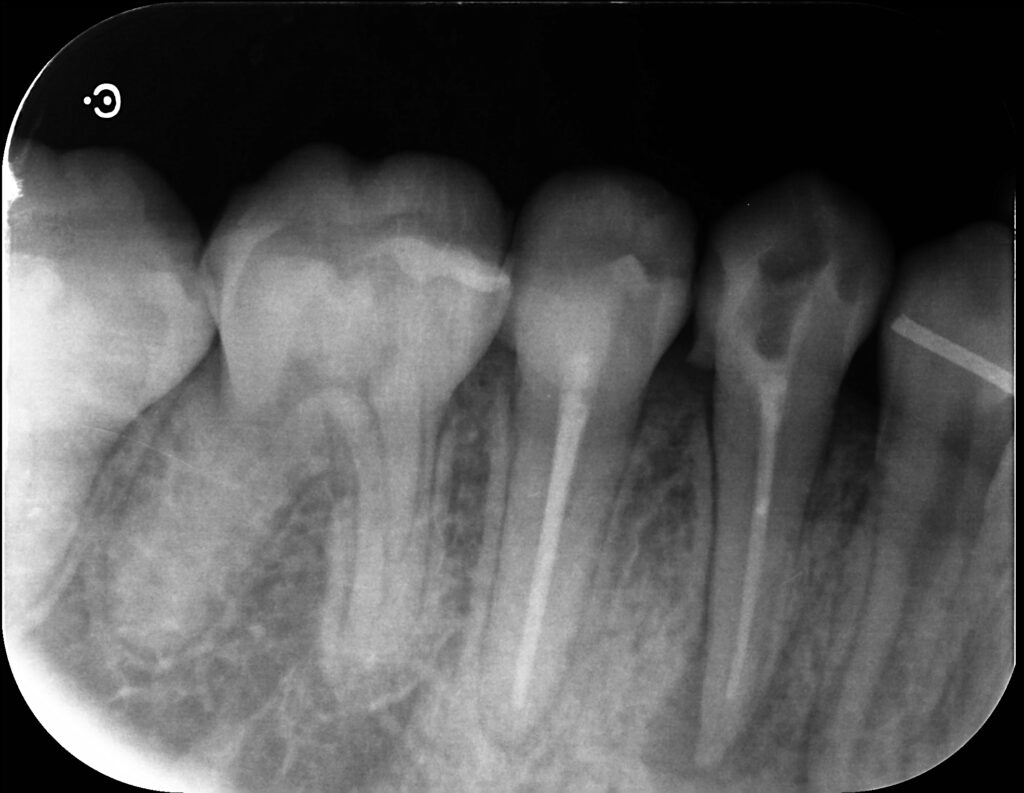

レントゲン

右下4番の根尖部に黒い透過像がありますね。(赤丸で囲ったところ)

聞くと、10数年前に治療したとのこと。

5番と同じく根尖までキレイに根充材は入っていますが‥

おそらく同じような時期に治療されたのかな?と思います。